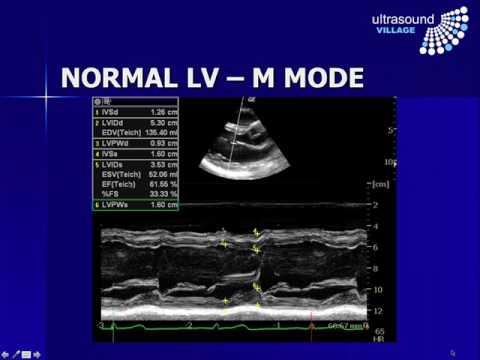

Estimating Ejection Fraction using Fractional Shortening with Cardiac Ultrasound/Echocardiography

How to measure the LEFT VENTRICULAR DIAMETER: Echocardiography!